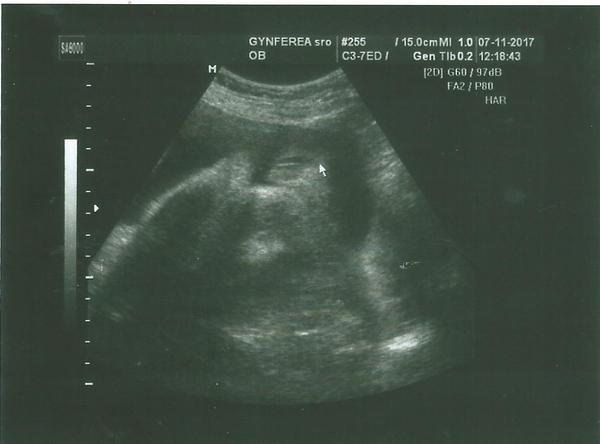

Pomýlil sa doktor pri určení pohlavia na 3D sone v 20 týždni?

Urcili mi na 90% chlapca ale ja mam stale pocit ze to bude dievca